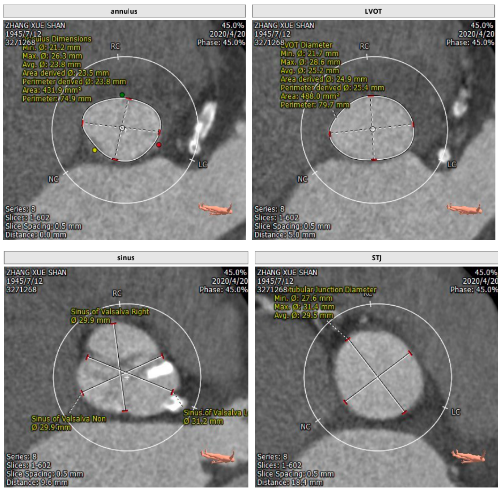

主动脉根部解剖: